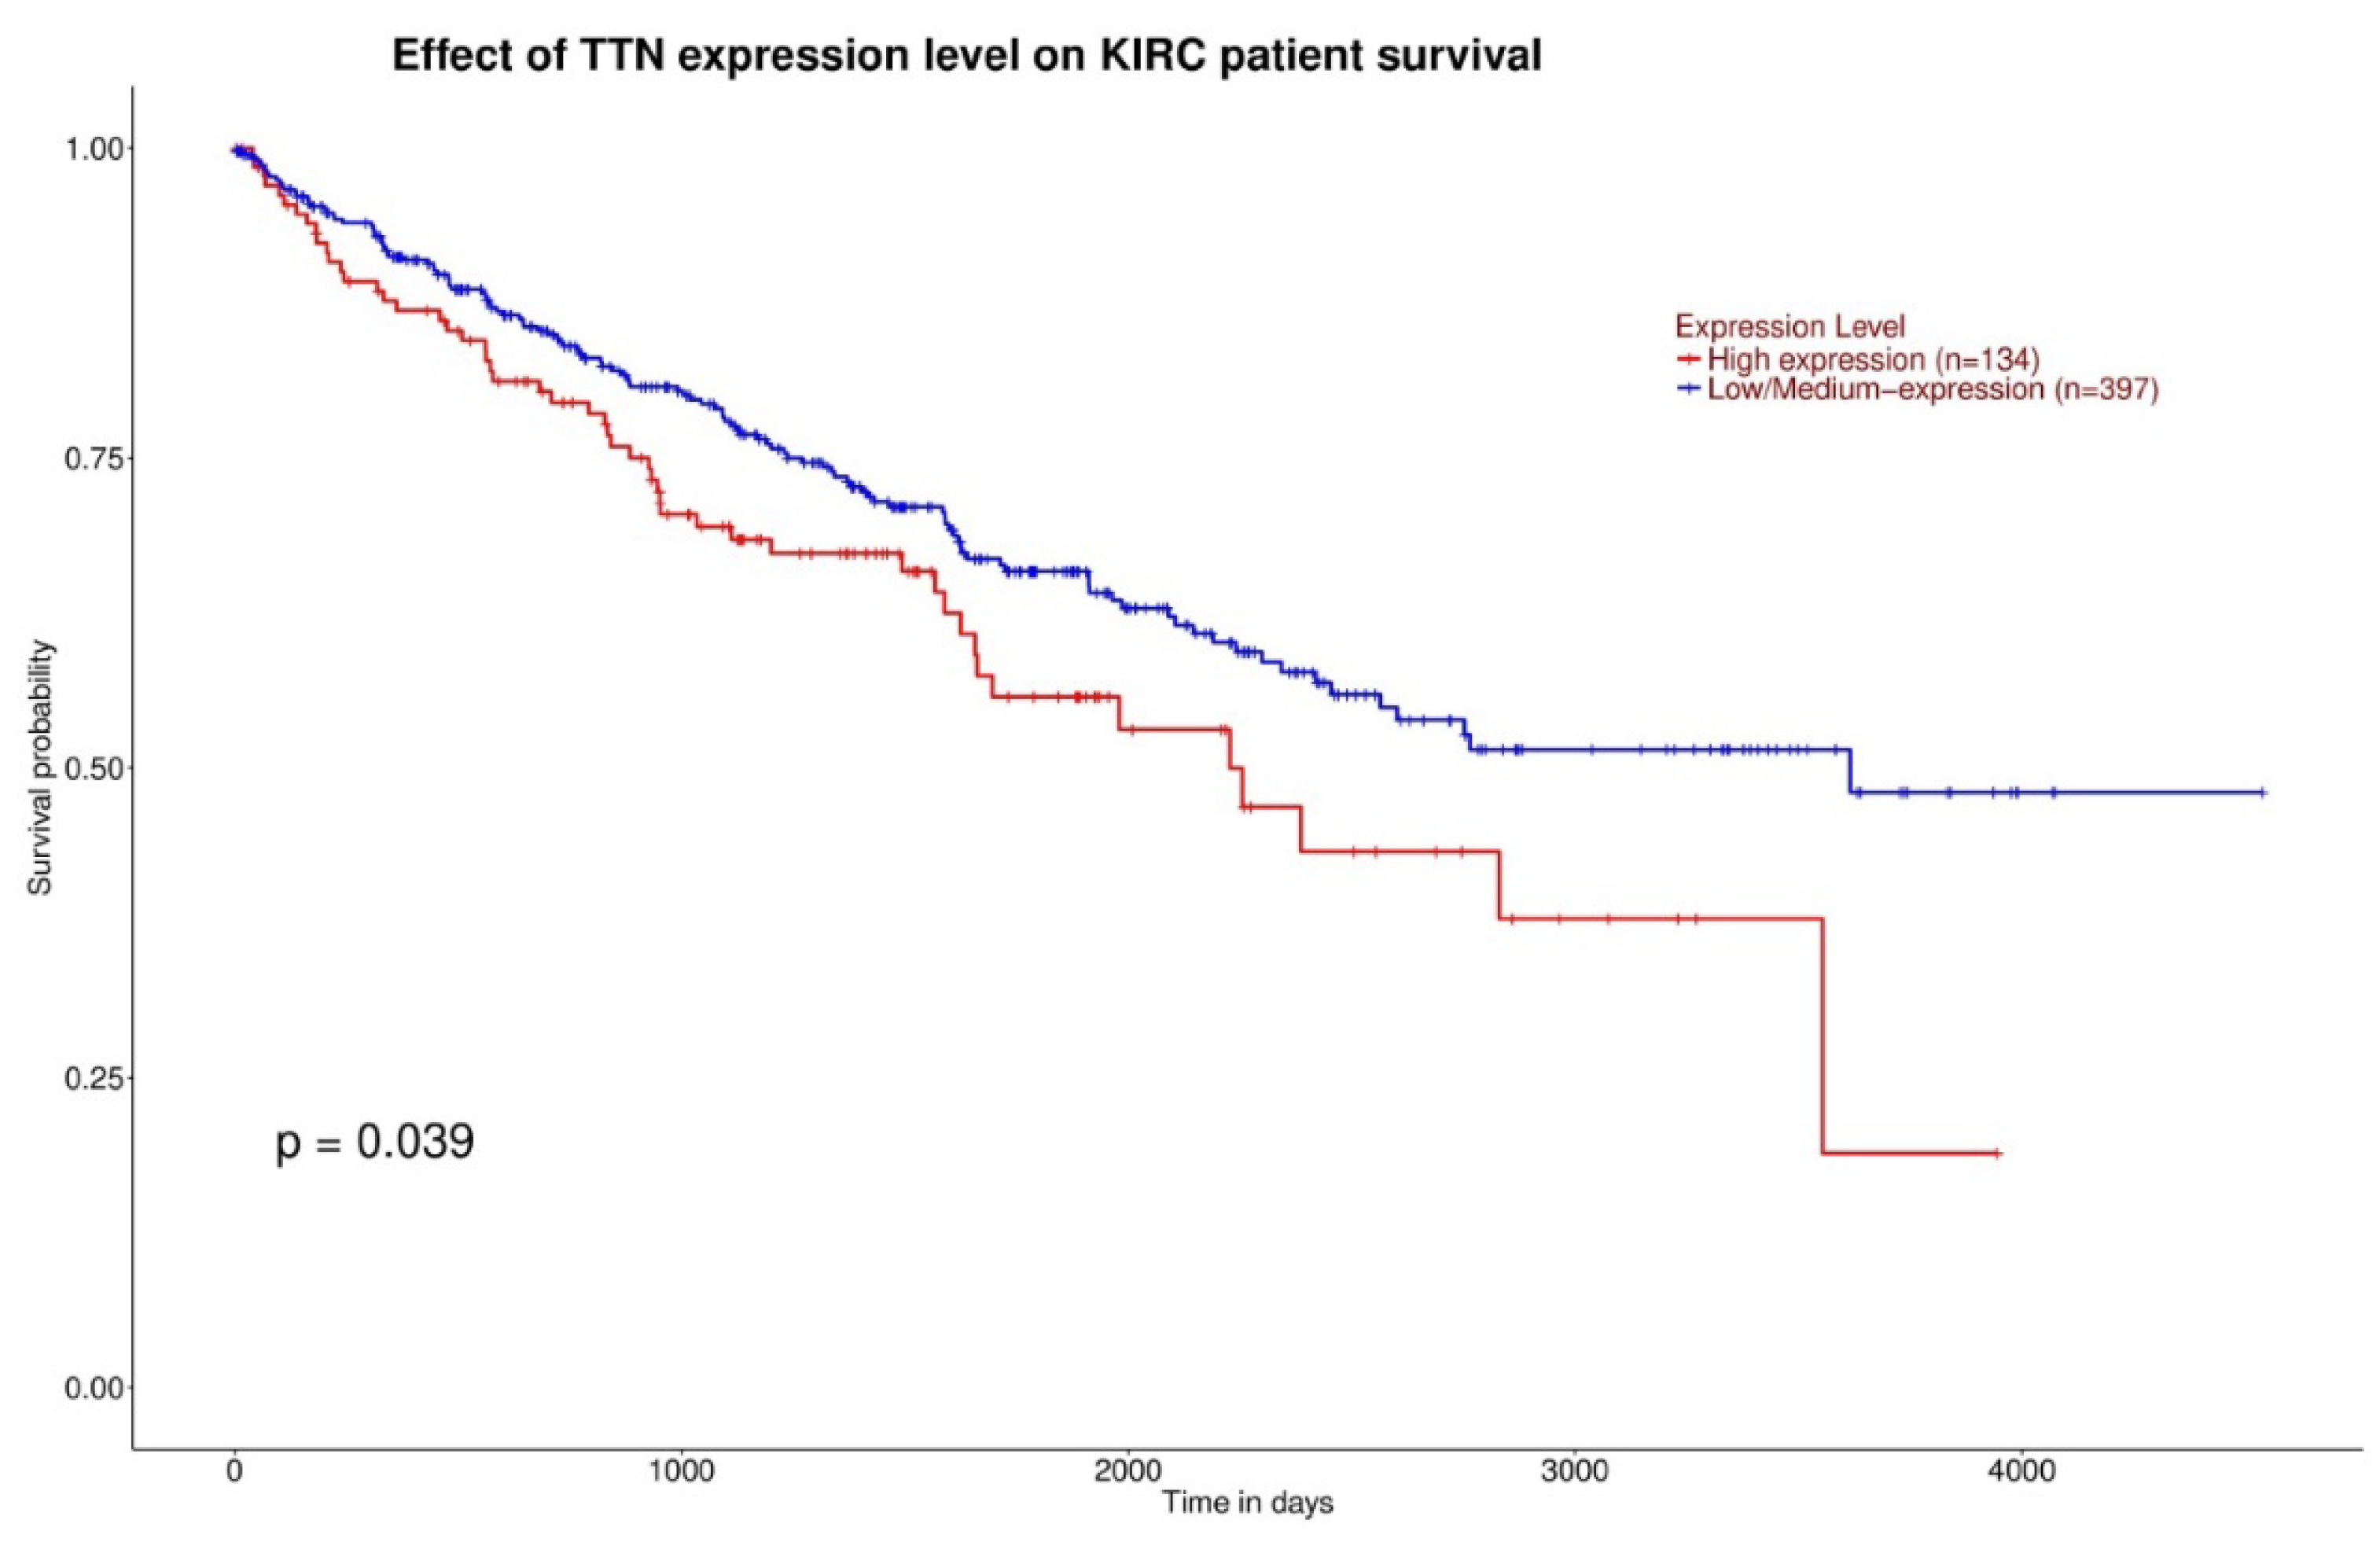

3.1. Gene Expression and Survival